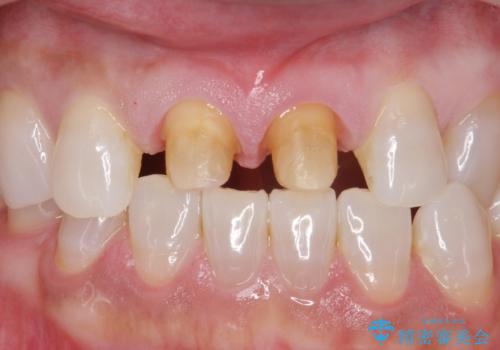

ラミネートべニアが取れた ジルコニアクラウンでの修復

- 前歯につけていたべニアが取れたとのことで来院された患者様です。

より脱離リスクの低いクラウンでの修復を行います。

取れていない方のべニアも周囲の歯と色調が合っていなかったため、一緒にやり替えました。